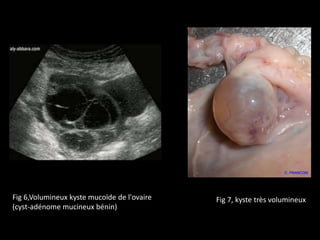

Fig 7, kyste très volumineuxFig 6,Volumineux kyste mucoïde de l'ovaire

(cyst-adénome mucineux bénin)

SOPK est biendifférent du simple kyste Un kyste de l'ovaire : ♀ Une petite poche, remplie d'une sorte de mucus. ♀ fréquents mais bénins et disparaissent spontanément, sans nécessiter de traitement.

Fig 7, kystetrès volumineuxFig 6,Volumineux kyste mucoïde de l'ovaire (cyst-adénome mucineux bénin)